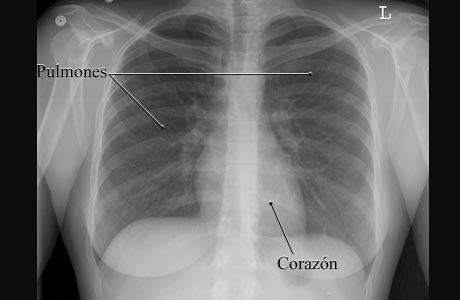

Radiografía de un pecho normal

Imagen de un pecho normal

Cortesía de Intermountain Medical Imaging, Boise, Idaho.

Esta es una imagen de una radiografía de pecho (tórax) normal de una mujer, que muestra los espacios llenos de aire de los pulmones y la forma gris más sólida del corazón. Los pulmones y el corazón son de tamaño y forma normales.